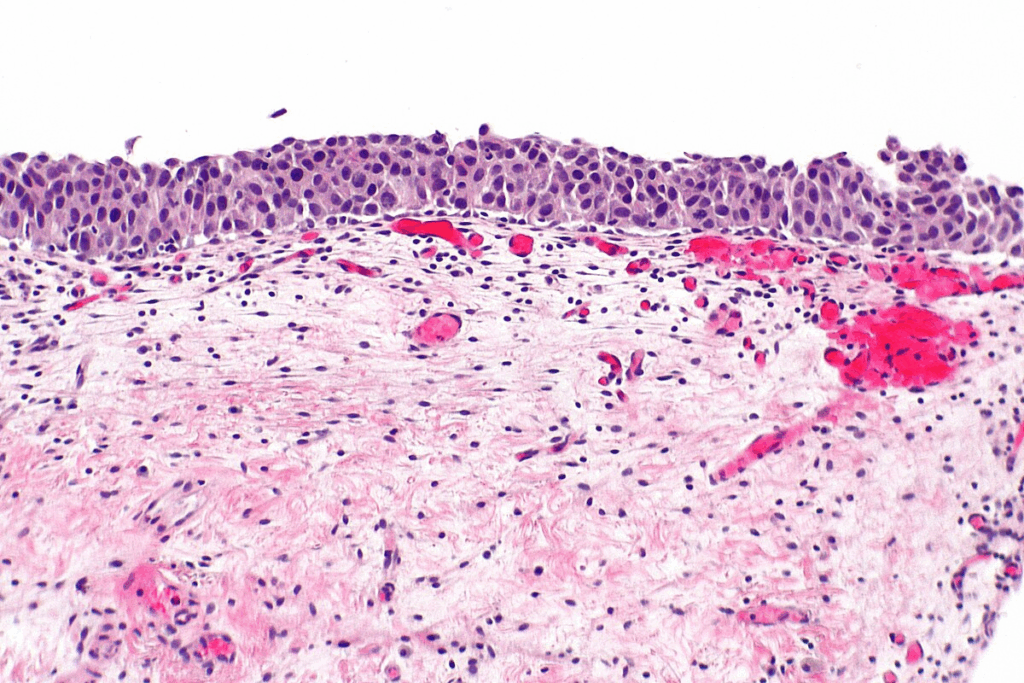

The term ‘in situ’ comes from Latin, meaning ‘in its place.’ It describes cells that stay in one place, within epithelial tissues. They haven’t invaded deeper or surrounding tissues. This stage is important because it means the cancer is contained and can be cured if treated right.

Cancer in situ is different from invasive cancer because it stays in one place. CIS hasn’t broken through the basement membrane. This means it hasn’t invaded deeper tissues or spread to other parts of the body. Knowing this is key for figuring out the cancer’s stage and treatment.

It’s important to understand the biology of cancer in situ to grasp its role in cancer diagnosis. Cancer in situ, or carcinoma in situ, is when cancer cells are present but haven’t spread to healthy tissues. These cells are different from normal cells, and knowing how they differ is key to treating cancer in situ.

Under a microscope, cancer in situ cells look different from normal cells and invasive cancer cells. The key features include:

Pathologists look at tissue samples to find these signs, which are vital for diagnosing cancer in situ.